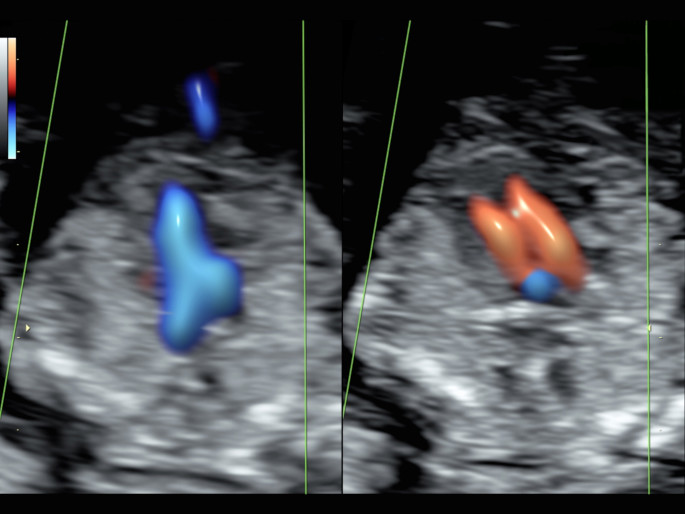

Weiterhin untersuchen wir den Blutfluss im Ductus venosus (Gefäßverbindung zwischen der Nabelvene und der unteren Hohlvene des Kindes) und den Blutfluss über der Trikuspidalklappe (Herzklappe zwischen dem rechten Vorhof und der rechten Herzkammer). Diese Parameter sind bei Feten mit einem Down-Syndrom gehäuft auffällig. Auch hier ist es wichtig zu wissen, dass auffällige Blutflüsse auch bei völlig gesunden Feten gesehen werden können. Diese zusätzlichen Parameter lassen sich nicht in jeder Untersuchungssituation vollständig dar-stellen.

Die fetale Echokardiographie dient der vorgeburtlichen Erkennung von angeborenen Fehlbildungen des Herzens:

Herzfehler zählen zu den häufigsten angeborenen Fehlbildungen und eine frühzeitige Diagnosestellung ermöglicht es, die weitere Überwachung der Schwangerschaft, Geburt und anschließende Versorgung optimal zu organisieren.

Hierbei werden Größe und Lage des Herzens, die Herzkammern und- klappen sowie die zum Herzen führenden und abgehenden großen Gefäßen und Venen beurteilt. Durch Ultraschalltechniken wie Farbdoppler, gepulster Doppler, M-Mode und 3D-Techniken (STIC) können ca. 85% aller angeborenen Herzfehlerentdeckt werden.